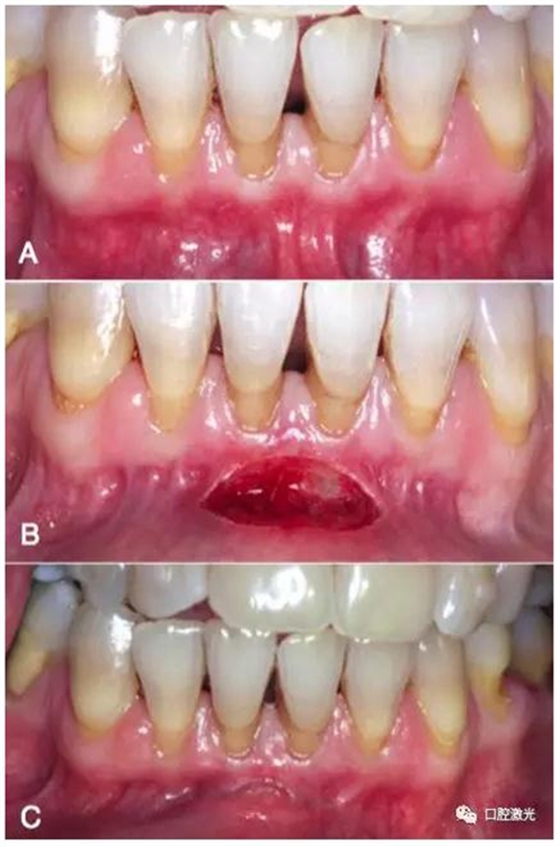

A:下唇系帶手術(shù)前

B:下唇系帶手術(shù)完成現(xiàn)場(chǎng)

C:手術(shù)完成一周后迅速恢復(fù)狀態(tài)